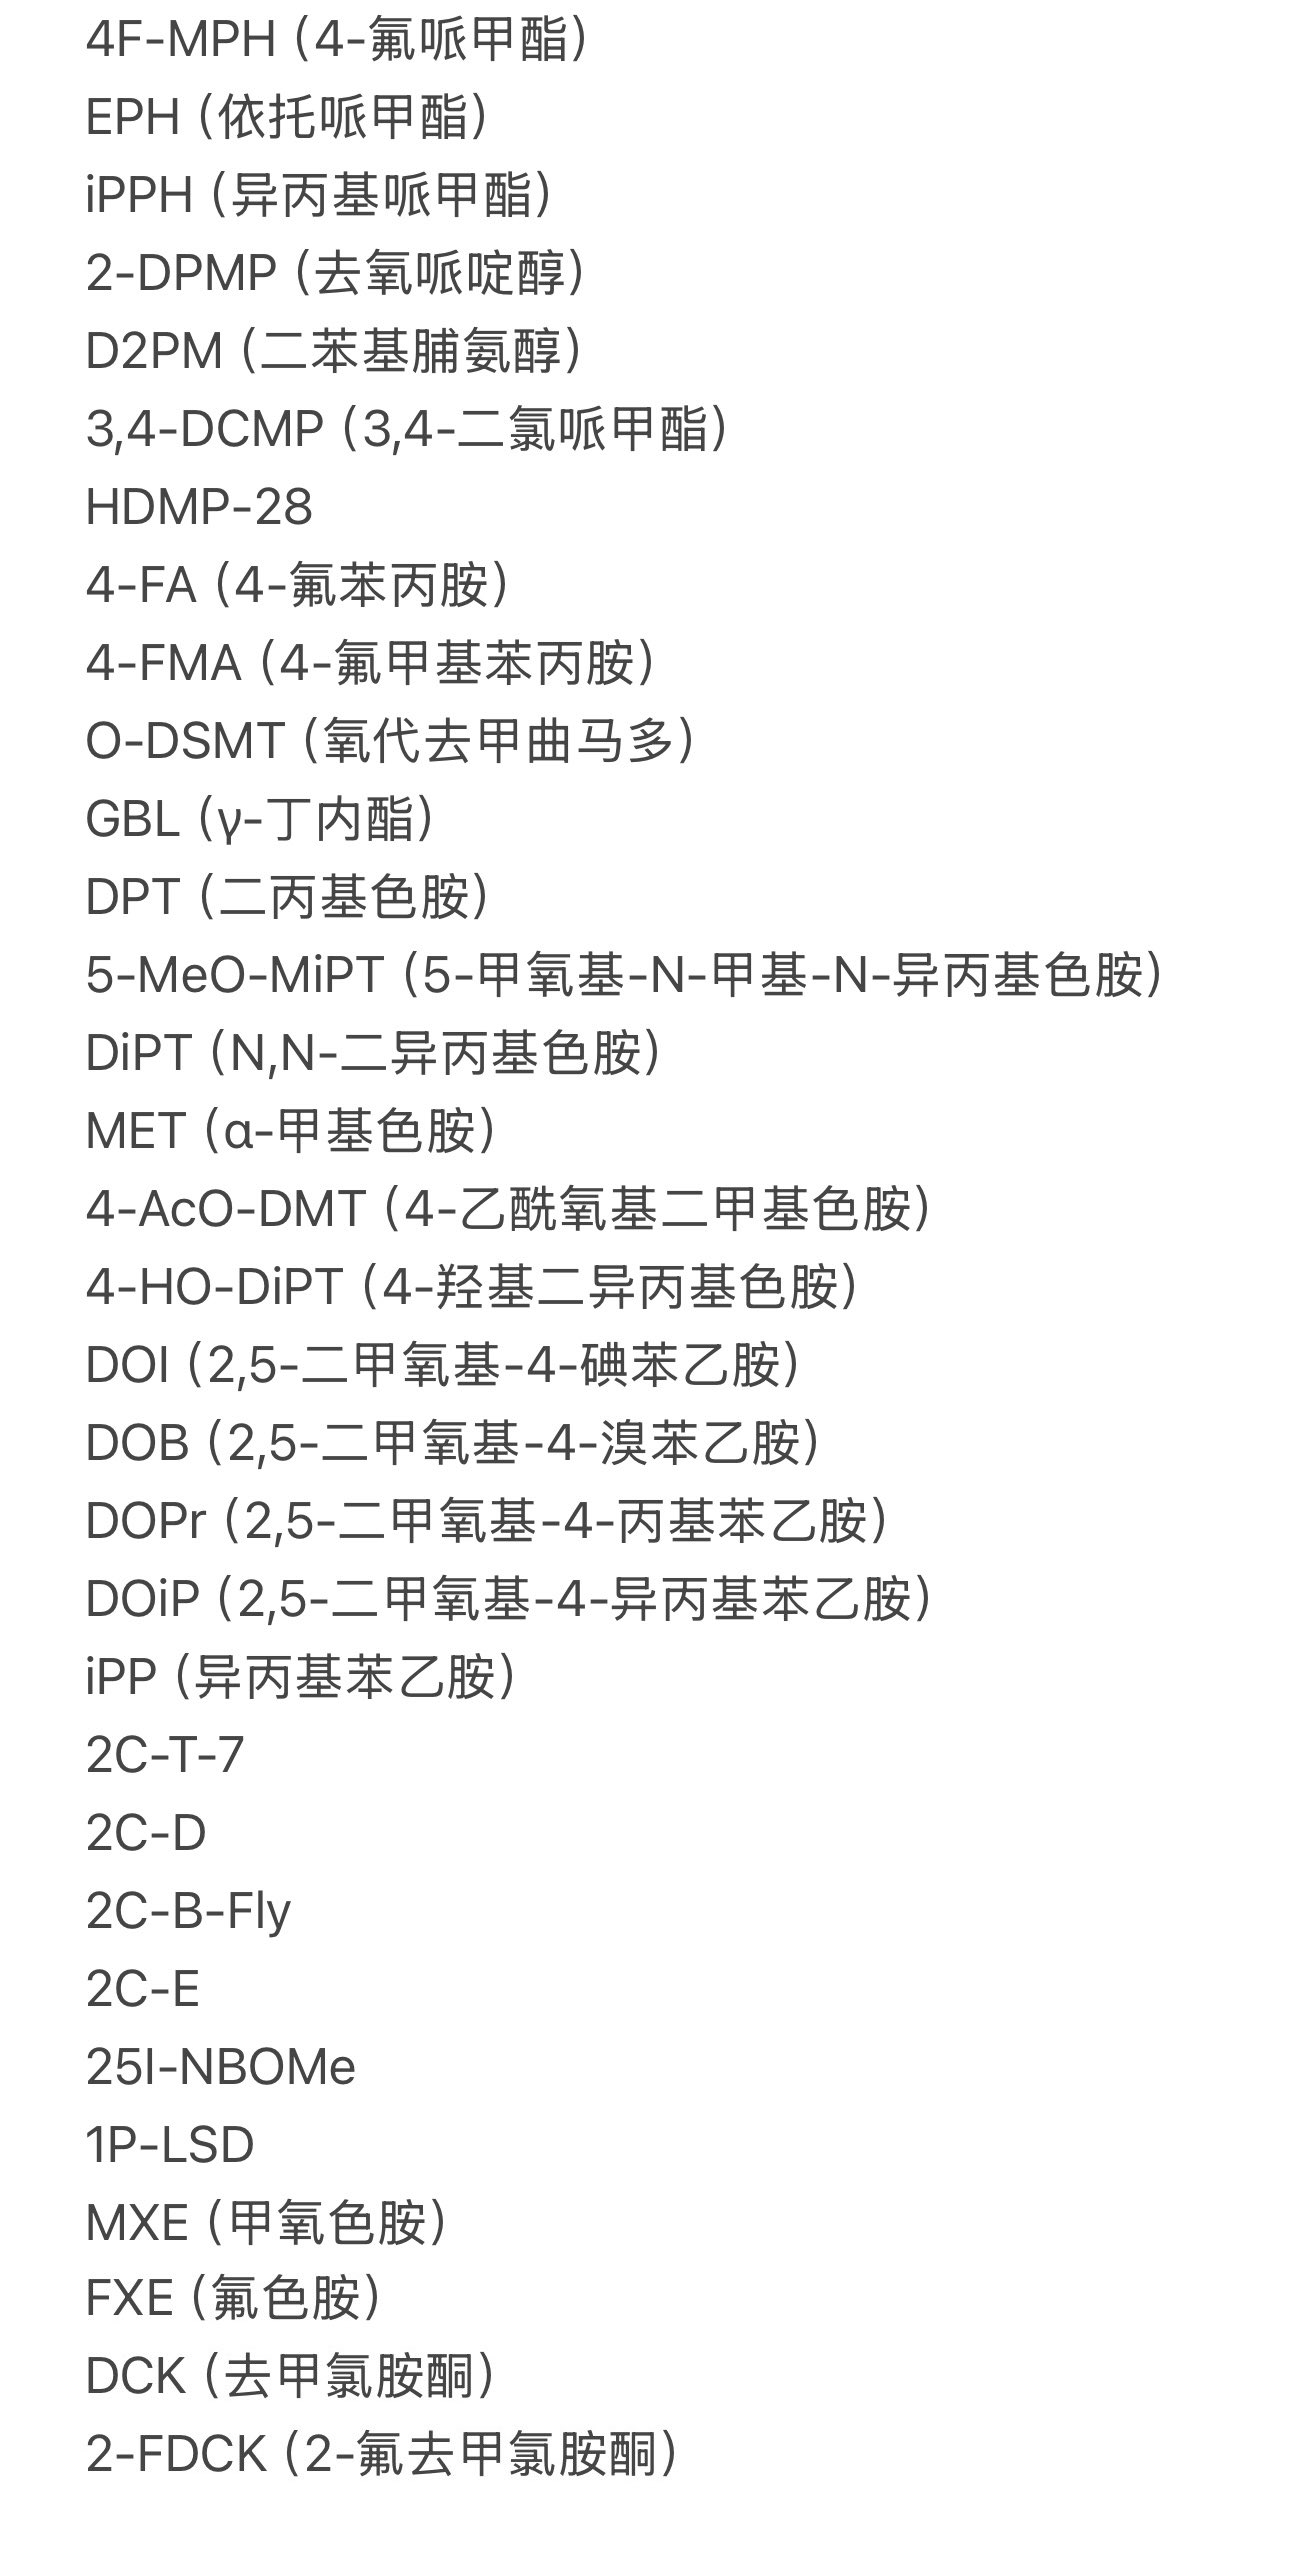

首先,从定义上讲,“反解离(anti-dissociative)”并不是一个标准的医学术语或者广泛认同的药理学分类。在正规资料,比如医学文献、维基百科、精神药理学教科书中,目前并没有“反解离药物”这个正式概念。

看上去像是为了描述某类特定效应而创造的术语(可能是nmda受体活性增强),用来对抗因NMDA受体拮抗剂(比如氯胺酮、DXM、PCP等)引发的解离体验(dissociation)。

那么更常见的是将其归入认知增强剂(cognitive enhancers),特别是改善认知连接性(connectivity)和现实感知(reality testing)的类型。

但其实在药理学上,单纯用“受体激动剂”来逆转“受体拮抗剂”的效应,有时会导致过度激活。

对于NMDA受体而言,过强的NMDA活化本身就与兴奋性毒性(excitotoxicity)和精神病样症状(psychotomimetic effects)有关,比如谷氨酸风暴可以引发严重的焦虑、妄想、乃至癫痫。

也就是说,简单地“激动-解除拮抗”在中枢神经系统是很危险的做法,尤其是对于易感个体(如有精神分裂素质的人)。

科学的处理方式一般是通过更细致的调节,比如微调NMDA/AMPA平衡、调节其他辅助途径(如GABA、5-HT、mGluR受体),而不是简单粗暴地用“NMDA增强剂”去顶回去。

而临床处理药物中毒中,其实医生更常用的做法是保守、支持性的治疗,比如补液,促进代谢,必要时镇静,以及监测生命体征防治并发症。

药物拮抗与受体激动之间,往往牵扯到的是复杂的适应性变化(receptor upregulation/downregulation),

不是简单的“给多一点刺激就能抵消”的关系

金刚烷胺会对神经系统造成长期/不可逆的影响

首先多巴胺系统

金刚烷胺作为多巴胺释放促进剂,在长期使用或过量下可能导致:

-DA系统适应性衰竭(Receptor downregulation)

-药源性多巴胺枯竭综合征:表现为认知退化、动机缺失(apathy)、情绪迟钝等。

NMDA

虽然金刚烷胺是弱NMDA拮抗剂,但长期使用可能导致:

-突触可塑性损伤(LTP/LTD受阻)

-情景记忆下降、学习能力减退

-焦虑、攻击行为升高

-神经元代谢负荷增加,增加兴奋毒性风险

金刚烷胺提高兴奋性毒性(NMDA活性失衡、多巴胺代谢紊乱),与致幻剂合用或交替用药会:

-加剧皮层-边缘系统的不稳定性(例如海马体、前额叶)

-增加精神病风险(psychosis risk)

-导致长期认知损伤与感知畸变的残留症状(HPPD-like states)

另外有导致神经适应性结构改变

动物研究提示,金刚烷胺长期使用可能导致:

-树突棘数量下降

-突触可塑性衰退

-神经炎症因子(如IL-6)升高,为不可逆脑损伤打下基础

它会干扰5-HT2A通路。血清素能致幻剂主要作用于5-HT2A受体,产生高级联想、幻觉和情绪增强等效果。

金刚烷胺干扰的是另一神经通路,但长期滥用会导致:

-5-HT2A介导的功能异常,表现为致幻剂效应变得怪异、碎片化或产生负面情绪。

-用户常报告“致幻剂效应被拉钝”“无乐感”,甚至致幻耐受的上升。